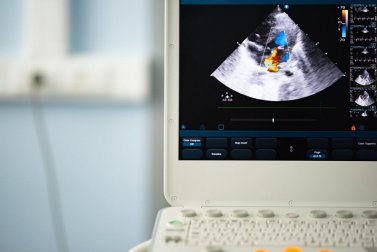

Durante a revisão, um estetoscópio pode ser usado para perceber palpitações cardíacas irregulares e algum sinal de sopro cardíaco. Em seguida, para verificar se estamos diante de uma válvula aórtica bicúspide, é realizado um ecocardiograma para avaliar como o coração está funcionando.